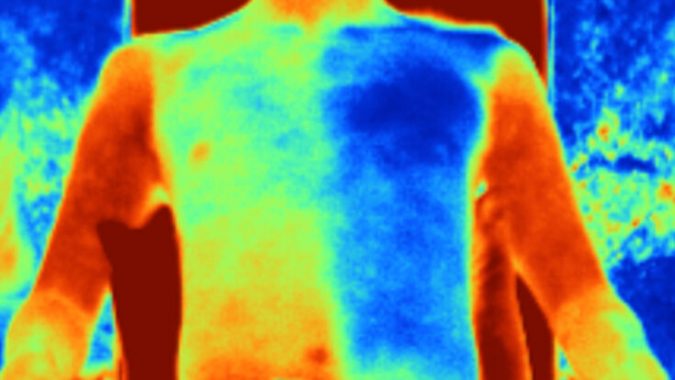

त्यानंतरच्या चाचण्यांत हे कापड आणि त्याचबरोबर नेहमीच्या वापरातली विविध प्रकारची कापडं, औष्णिकदृष्ट्या मानवी त्वचेशी साधर्म्य असणाऱ्या पृष्ठभागावर ठेवण्यात आली. मध्यान्हीच्या उन्हात ठेवल्यानंतरही या कापडाचं तापमान सुती कापडाच्या तुलनेत सुमारे पाच अंश सेल्सियसनं कमी तर, लिननच्या कापडाच्या तुलनेत ते सुमारे सहा अंश सेल्सियसनं कमी भरलं. हा प्रयोग प्रत्यक्ष एका स्वयंसेवकावरही करण्यात आला. या स्वयंसेवकाला एक जाकीट घालायला दिलं आणि त्याला मध्यान्हीच्या उन्हात बसवलं. या जाकिटाचा अर्धा भाग या ‘थंड’ कापडापासून बनवलेला होता आणि उर्वरित अर्धा भाग बाजारात मिळणाऱ्या सुती कापडापासून बनवला होता. या जाकिटाच्या आतील तापमानाचं मापन केलं गेलं. दोन्ही भागातल्या तापमानांत सुमारे पाच अंशांचा फरक होता!